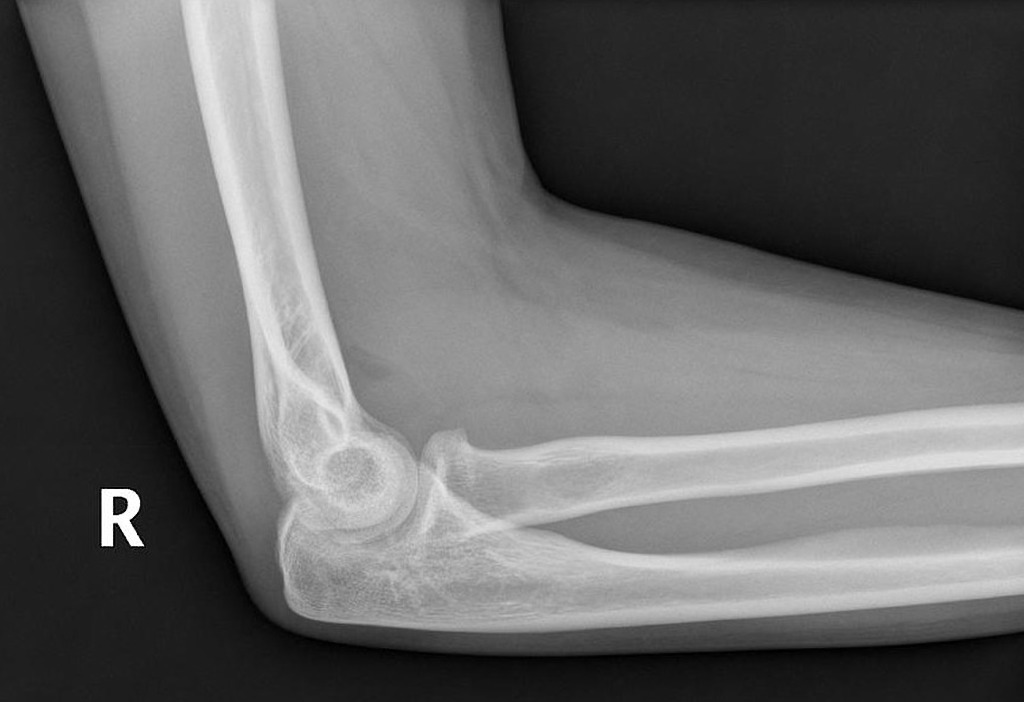

What is the posterior fat pad sign?

a lucent crescent of fat located in the olecranon fossa on a true lateral view of an elbow joint with the elbow flexed at a right angle

What does a posterior fat pad sign indicate? What should you look for in adults? In children?

Indicates an elbow joint effusion that suggests a non-displaced fracture

In adults: radial head fracture

In children: supracondylar fracture

What is the anterior fat pad sign?

The elevation fof the anterior fat pad to create a silhouette

What does an anterior fat pad sign indicate? What should you look for in adults? Children?

Joint effusion as anterior fat pad is elevated away from humerus –> intra-articular fracture